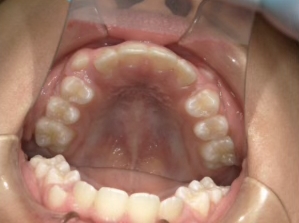

治療中⑤ 小5:10y11m

モノブロック装置継続中、左上3が八重歯で萌出